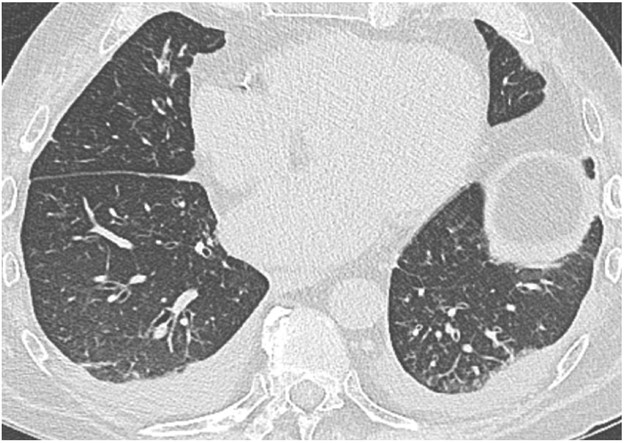

The clinical and imaging manifestations of pneumonia in transplant recipients are similar to those of nontransplant patients. Lung transplant recipients who present with dyspnea, cough, or fever are evaluated for pneumonia. Imaging findings of pneumonia include consolidation, ground-glass opacities, septal-line thickening, and pulmonary nodules. Pulmonary nodules can be single or multiple; they may be solid or ground-glass in attenuation. Cavitary nodules and nodules with ground-glass halos can occur, especially in patients with fungal pneumonia. Imaging studies should be scrutinized for complications of infection such as pulmonary abscess and bronchopleural fistula. Patients may also have reactive pleural effusions or reactive mediastinal or hilar lymphadenopathy. Treatment is the same as in nontransplant patients and consists of antibiotics, antivirals, or antifungals depending on the causative pathogen. Figure 4 shows three different lung transplant recipients with pneumonia.